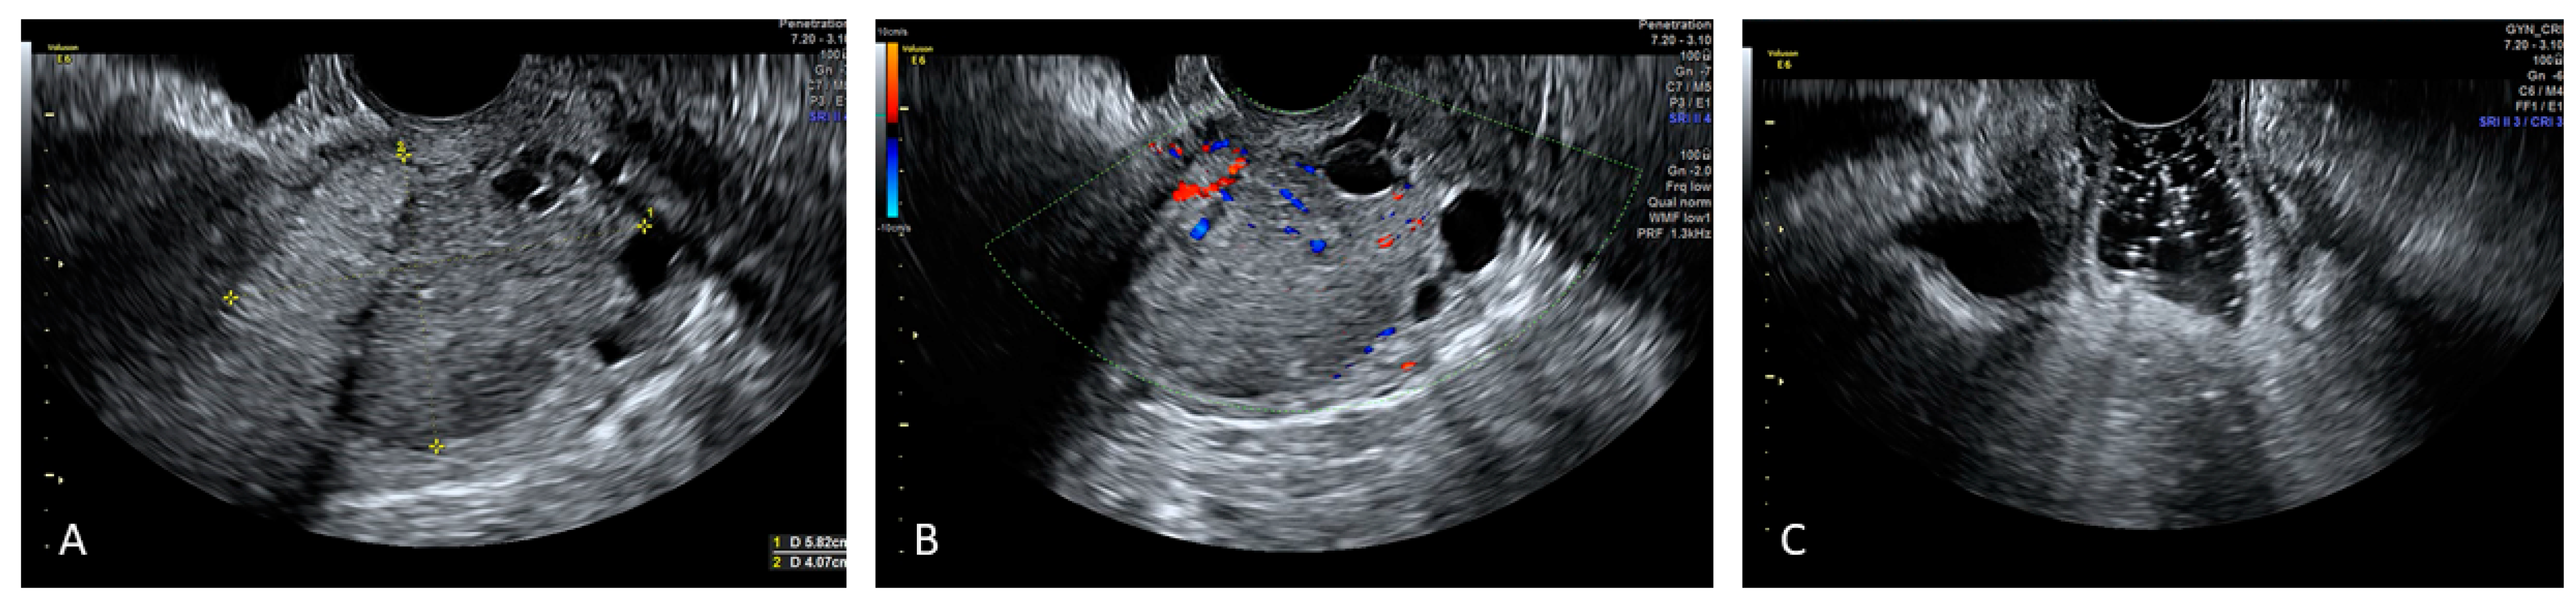

Figure 4. Reports the SVG image of a mixed echogenicity cervical cancer lesion whose caudal limit is delimited by nabothian cysts (Panel (A)) and its vascularization (Panel (B)). SVG reveals regular vaginal walls (Panel (C)).